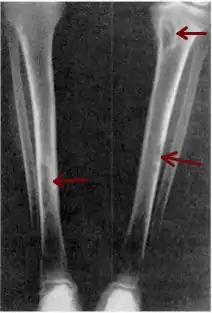

| Osteitis fibrosa cystica of the tibia. Arrows point to the brown tumors which are typically present in bones of people with OFC. | |

X-rays may also be used to diagnose the disease. Usually, these X-rays will show extremely thin bones, which are often bowed or fractured. However, such symptoms are also associated with other bone diseases, such as osteopenia or osteoporosis.[29] Generally, the first bones to show symptoms via X-ray are the fingers.[22] Furthermore, brown tumors, especially when manifested on facial bones, can be misdiagnosed as cancerous.[29] Radiographs distinctly show bone resorption and X-rays of the skull may depict an image often described as "ground glass" or "salt and pepper".[30][31] Dental X-rays may also be abnormal.[2]